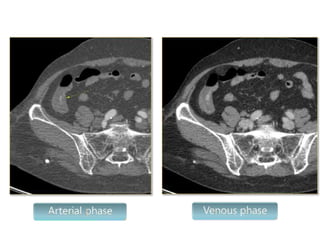

Multidetector Row CT (MDCT)

 Show contrast extravasation into any portion of the

gastrointestinal tract

 Detects bleeding rates as low as 0.3 to 0.5 ml per minute

 The average yield of MDCT for lower GI bleed Is 60%, with yields

ranging from 25% to 95%.

 Lack of therapeutic capability is a major limitation

 Useful in guiding further:angioembolisation